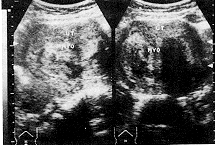

子宫肌瘤变性的声像图特点:(1)玻璃样变:病变切面失去旋涡状结构变为同质、其回声较为衰减(图1)。本组有3例占1.84%;(2)红色变性:为一种特殊型肌瘤坏死,常发生于较大的肌瘤中,妊娠期或产褥期易发生此种变性,切面呈肉红色、保持旋涡状外形,声像图上肿瘤明显衰减,界限不清(图2)。本组有5例占3.06%;(3)囊性变:当玻璃样变继续发展、液化形成许多大小不等的空腔,也可融合成一大囊腔,囊腔内壁光滑、囊内含液体多无色透明。前者有时很像葡萄胎,后者酷似卵巢囊肿,仔细观察瘤体的非囊区仍可见肌瘤的特点,回声较强,亦可以很弱或杂乱(图3,4)。本组有4例,占2.45%;(4)钙化:多发生于玻璃样变坏死后、由于肌瘤血液循环障碍、钙盐被组织成分及其他变性物质所吸收而沉积,超声图像显示为增强的回声团其后伴声影。本组有3例占1.84%。

图2 子宫肌瘤间平滑肌瘤 图3 子宫肌瘤(肌壁间)伴变

伴灶性红色变性(病理证实) 性(黄色粘冻样物)(病理证实)

UT:子宫,MYO:肌瘤 IUD:避孕器